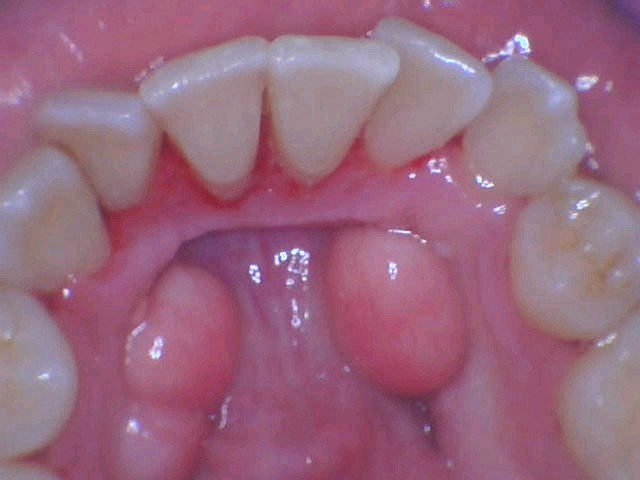

- Soft Tissue Grafting

Losing gum tissues also recedes your gum line. We perform soft tissue grafting to help you retain and maintain your gum line. The procedure involves removing a small amount of tissue from your mouth’s roof and attaching it to the site of the surgery. Apart from retaining your gum line, soft tissue grafting keeps further gum recession at bay.